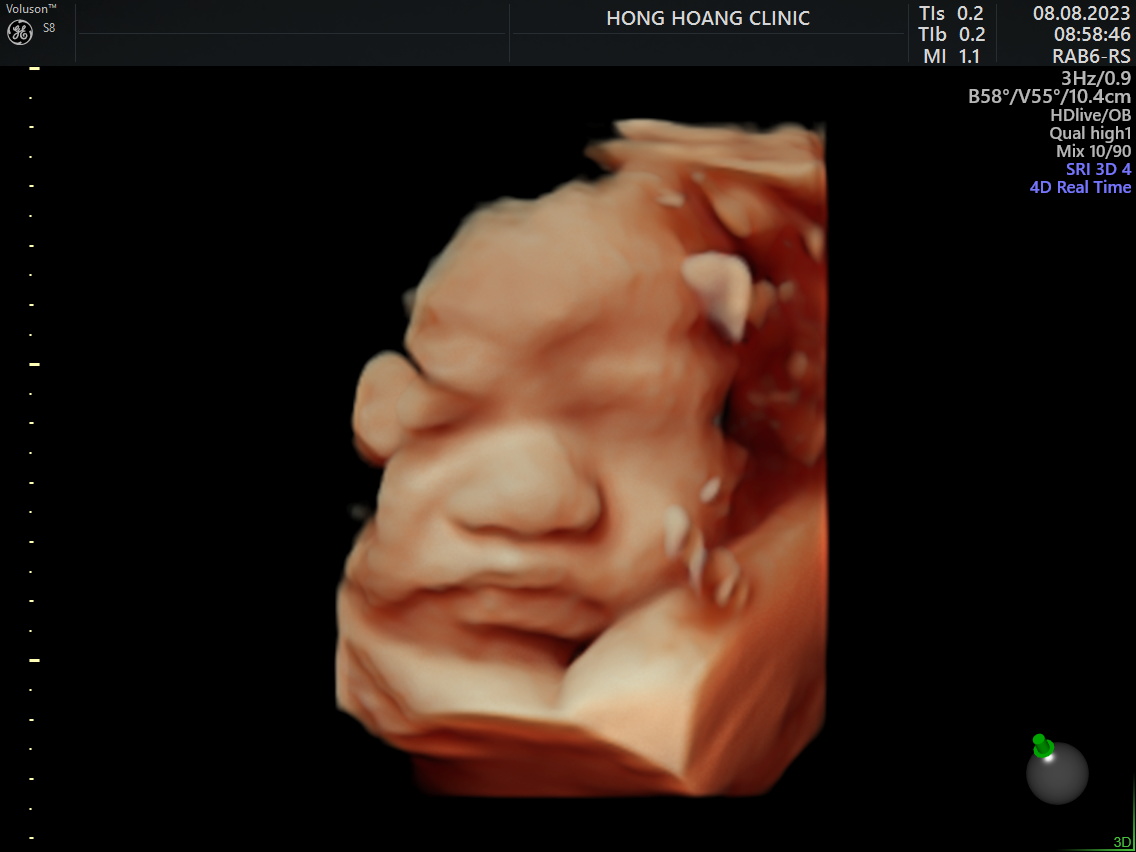

Siêu âm thai định kỳ - Con khỏe mẹ an tâm

Siêu âm thai 5D ngay tại Hồng Hoàng các mẹ nhé!